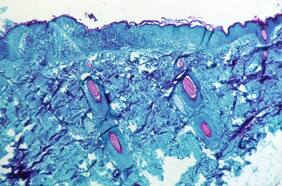

Debido a la muerte de millones de visones en Europa, contagiados con el nuevo coronavirus, especialistas de la U. de Chile analiza la posibilidad que algún animal salvaje en Chile pueda contagiarse y convertirse en un vector y transmisor de la enfermedad.

¿Qué posibilidades hay que animales que viven en Chile provoquen una nueva pandemia?